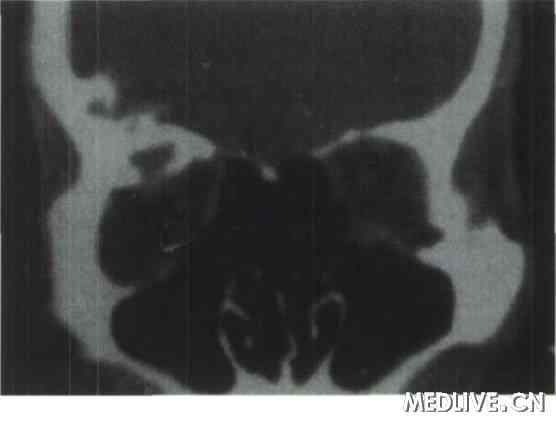

例1

患者男性,48岁,因左眼球突出伴视力下降1年1988年8月30日入院。体检: 全身情况无特殊。眼部检查:裸眼视力右眼0.9,不能矫正;左眼0.1,戴+ 1.00 DS矫正至0.3。双眼晶状体皮质轻度混浊,眼底检查示左眼后极部包括黄斑区有放射状脉络膜皱褶,右眼底无特殊表现。眼球突出度:右眼12 mm,左眼16mm, 眶距100mm,眶缘触不到肿物,双眼正位,眼球运动正常。眼底荧光素血管造影检查:提示左眼后极部条纹状高荧光,符合脉络膜皱褶。A型超声波检查提示: 左眶颞侧球后有一中高波反射,实性占位性病变波形。眼眶X线平片提示左眼眶上部见一高密度组织影,密度不均,呈细网状,边界清楚(图1)。CT检查示左眼眶外侧壁蝶骨大翼处见一软组织块影,大小为2.1cm×1.8 cm,CT值55~65 Hu, 左蝶骨大翼骨质呈膨胀性改变,骨质不规则增厚并向周围膨胀,左眼球向前内移位,眼环正常,无骨质破坏(图2)。入院诊断:(1) 左眼眶肿物;(2) 双眼老年性白内障初发期;(3)左眼屈光不正。于1988年9月4日在局部麻醉下行左眼外下方穹隆部结膜切口+外眦部皮肤切开前路开眶肿物摘除术,术中见外侧眶内有一3. 0 cm×2. 5 cm×1. 5 cm紫红色肿物,锥形,边界清楚,触之易出血,肿物与外侧骨壁相连,且相连处骨质增生,将肿物连同增生骨质切除后见骨壁呈蜂窝状改变,用骨蜡填充骨壁缺损后分层缝合。术后组织病理学诊断为:左眼眶蝶骨内海绵状血管瘤。术后6个月复查:右眼视力0.9,不能矫正,左眼视力0.3,不能矫正;眼球突出度:右眼12 mm,左眼13 mm;眶距100 mm,双眼正位,眼球运动正常。

图2 眼眶骨内海绵状血管瘤患者CT检查可见左眼眶外侧壁蝶骨大翼处见一软组织块影,大小为2.1cm×1.8cm,CT值55~65Hu,左蝶骨大翼骨质呈膨胀性改变,骨质不规则增厚并向周围膨胀